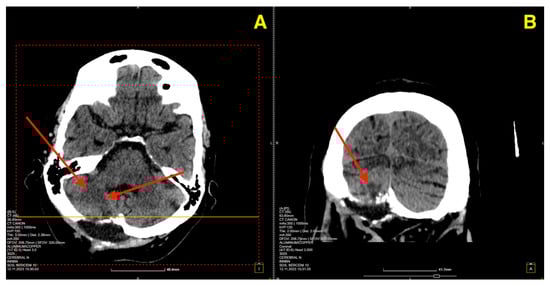

On postoperative day 5, a follow-up CT scan (Figure 3) was performed to assess the surgical site and confirm the absence of postoperative complications such as hemorrhage or hydrocephalus.

Figure 3. Five days post-op CT scan. (A) Demonstrated normal postoperative changes in the right paramedian posterior fossa. The site of the craniectomy was clearly visible, and no signs of residual cavernous malformation were observed. There was no evidence of acute hemorrhage, mass effect, or significant edema in the surrounding cerebellar tissue. Additionally, the ventricular system appeared normal, with no signs of hydrocephalus or midline shift. (B) provided further confirmation of the integrity of the bony structures and the absence of any complications related to the craniectomy. The surgical site remained stable, and there was no abnormal fluid collection or air entrapment within the resection cavity.

The two-month postoperative CT scan (Figure 4) confirmed excellent surgical outcomes. The right cerebellar hemisphere, where the cavernoma had been resected, demonstrated normal postoperative changes, with no signs of residual cavernous malformation or new lesions. The surgical cavity appeared stable, and no signs of hemorrhage or fluid collection were noted.

Figure 4. Two-month follow-up post-op CT scan. (A): Axial CT image of the right cerebellar hemisphere shows normal postoperative changes (red arrows) in the area of the cavernoma resection, with no residual cavernous malformation, new lesions, or signs of fluid collection or hemorrhage. (B): Coronal CT image further confirms the stability of the surgical cavity (red arrow), with no evidence of hemorrhage, recurrent lesions, or abnormal findings in the surrounding structures.